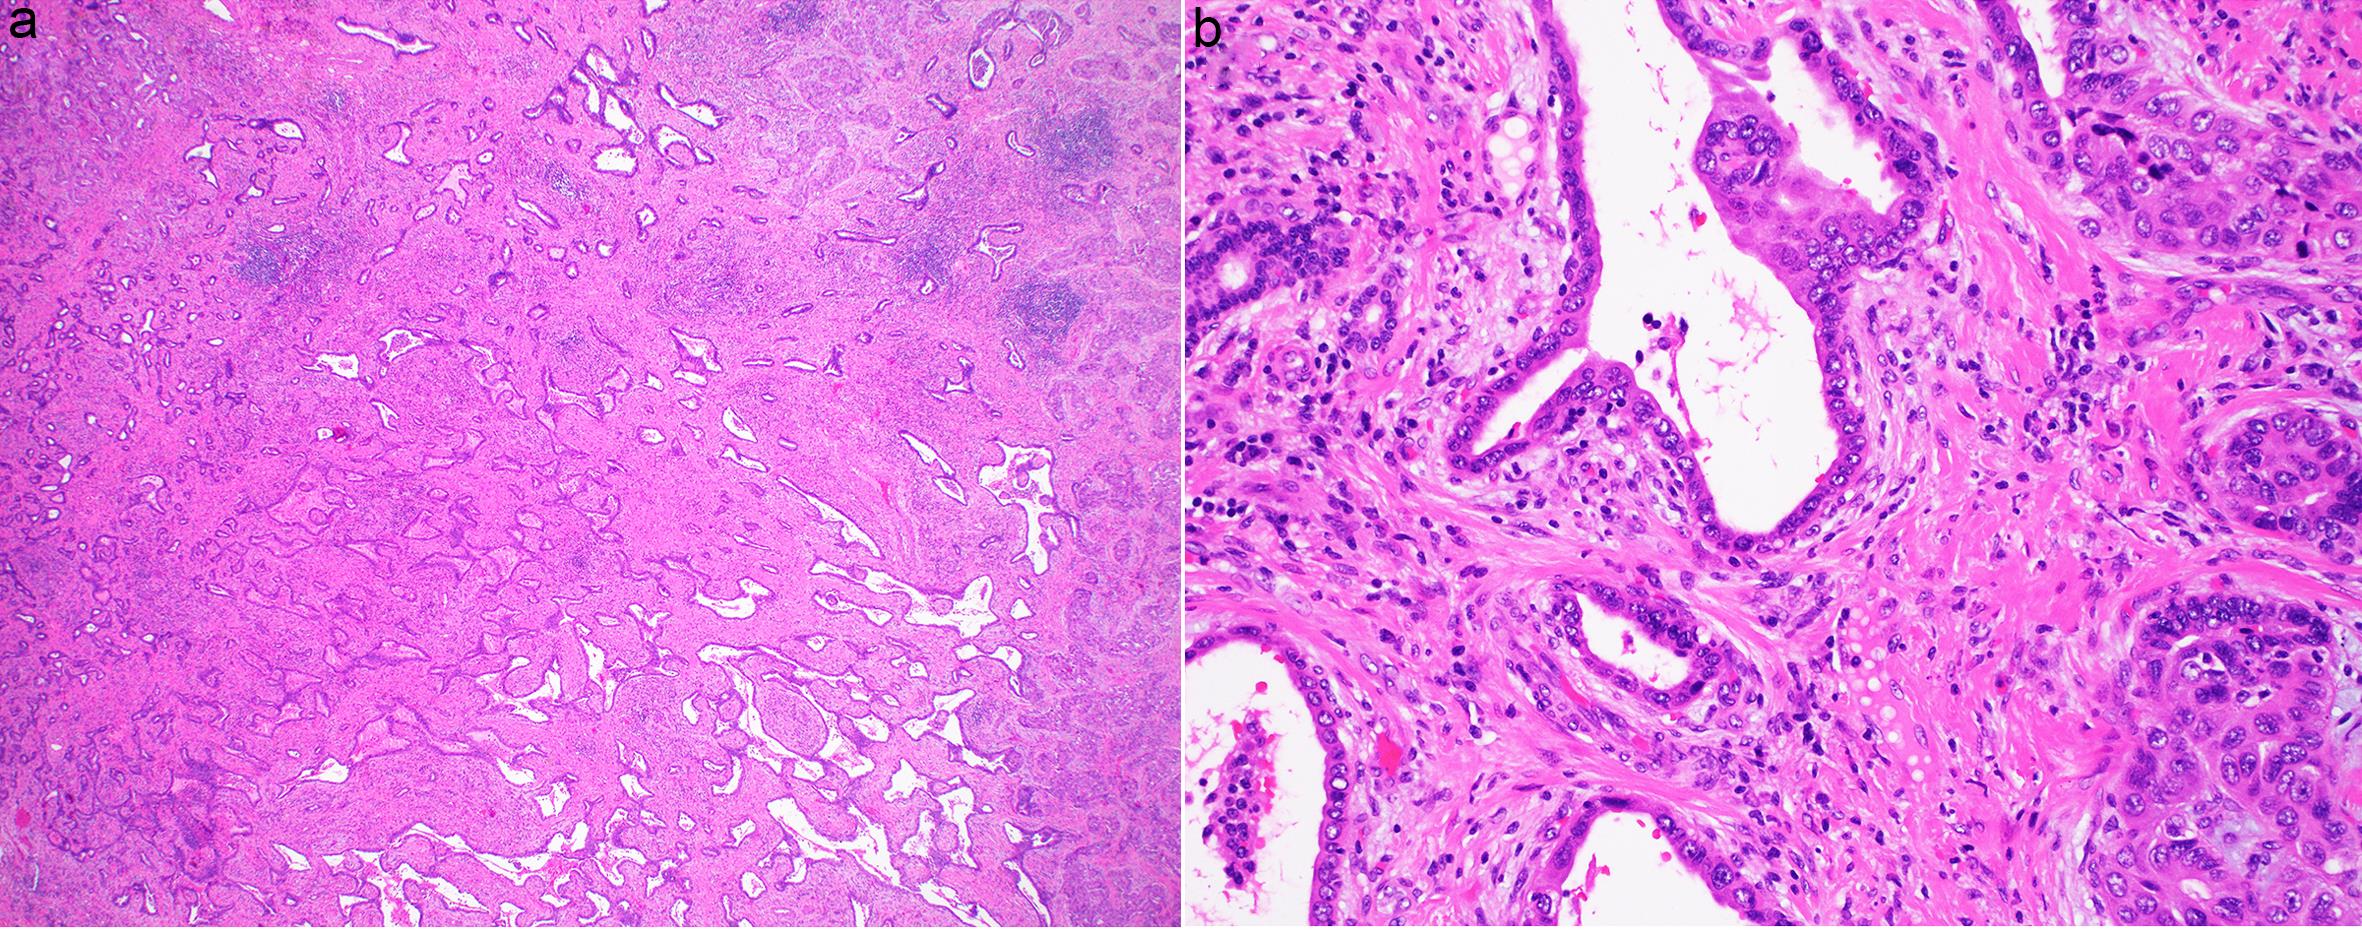

Neoplasms arising from the biliary system in the liver can be benign, borderline, or malignant. Intrahepatic cholangiocarcinoma (iCCA) refers to malignant bile duct tumors, accounting for approximately 10–15% of primary liver cancers, second only to hepatocellular carcinoma.1,2 iCCA may arise from borderline tumors or precursors such as biliary intraepithelial neoplasms. Benign biliary tumors commonly include von Meyenburg complexes (VMC), bile duct adenomas (BDA), biliary cysts, or cystadenomas (mucinous cystic neoplasms (MCNs)).3 Hepatic biliary adenofibroma (BAF), on the other hand, is an extremely rare benign bile duct tumor featuring low-grade tubuloglandular structures lined by a single layer of biliary epithelium and supported by abundant collagenous stroma, which is the origin of its name.4,5 Fewer than 25 cases have been documented in the English literature since the first case of BAF was reported three decades ago.4,6–9 Over the past decades, only one case fulfilling the morphologic criteria was retrospectively identified in the pathology databases of the two tertiary medical centers with which the authors are affiliated (Fig. 1a). The tumor exhibited a low Ki-67 proliferation index of less than 10% in both the epithelium and stroma, a characteristic feature supporting its diagnosis (Fig. 1b). Despite official recognition in the World Health Organization 5th edition for tumors of the digestive system as a distinct benign biliary tumor and precursor lesion to iCCA,5 the rarity of BAF continues to pose significant diagnostic challenges and raise unresolved questions, fueling ongoing interest and controversy surrounding this entity. This review aimed to enhance understanding of the histopathological and molecular features of BAF while outlining future research directions.

A rare case of biliary adenofibroma showing proliferation of individual biliary tubules and microcystic structures within a fibrous stroma (a). The tumor shows an extremely low Ki67 proliferation index in both the epithelium and stroma (b).

Fig. 1  A rare case of biliary adenofibroma showing proliferation of individual biliary tubules and microcystic structures within a fibrous stroma (a). The tumor shows an extremely low Ki67 proliferation index in both the epithelium and stroma (b).

Magnification: a: 40×; b: 200×.

Nearly a decade later, a second case of BAF was reported in a 47-year-old woman, presenting as a 16-cm solid and cystic liver mass with a histologic appearance similar to the first case, which also followed an indolent course.9 Over time, more cases were reported, with the largest case series comprising six patients, with a mean age of 60 years (range: 37–83 years) and a slight female predominance (F:M = 2:1). The masses, located in either the right or left hepatic lobes, were round to oval and ranged in size from 1.7 to 16 cm. The cut surface showed both solid and microcystic components in varying proportions, with a sponge-like appearance. Histologically, all masses displayed cystic/microcystic and tubular/glandular structures lined by low columnar and cuboidal non-mucin-producing biliary epithelium, similar to the initially reported case and our own (Fig. 1). Although immunohistochemical staining is not necessary for diagnosis, the epithelial cells were positive for AE1/3, CAM5.2, CK7, CK19, CEA, and EMA, which are typical of a biliary phenotype. Notably, none of the cases exhibited malignant features. Despite recurrences in two cases, all patients followed a benign or indolent course after excision, with no associated deaths.9